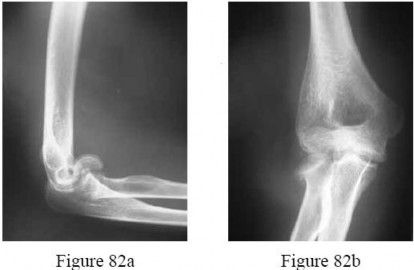

-are the radiographs of a 52-year-old woman who fell down the stairs and sustained an acute hemarthrosis of the elbow. What is the most common complication following surgical treatment of this injury?